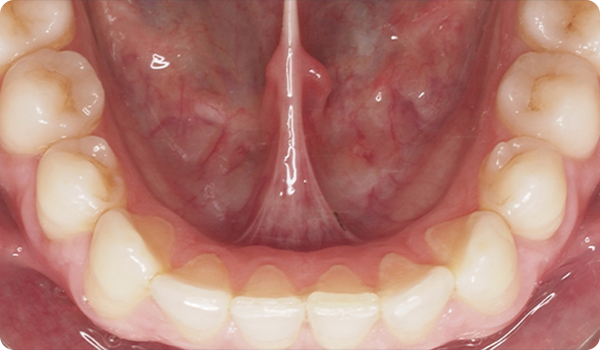

Sourires en place

Grâce à Right, vos patients obtiendront le sourire qu'ils souhaitent quand ils le souhaitent, de manière confortable et indétectable.

L'alignement des dents avec Right est la solution parfaite et la plus conservatrice pour les futurs traitements de blanchiment ou de facettes. Elle apportera la perfection au sourire du patient.